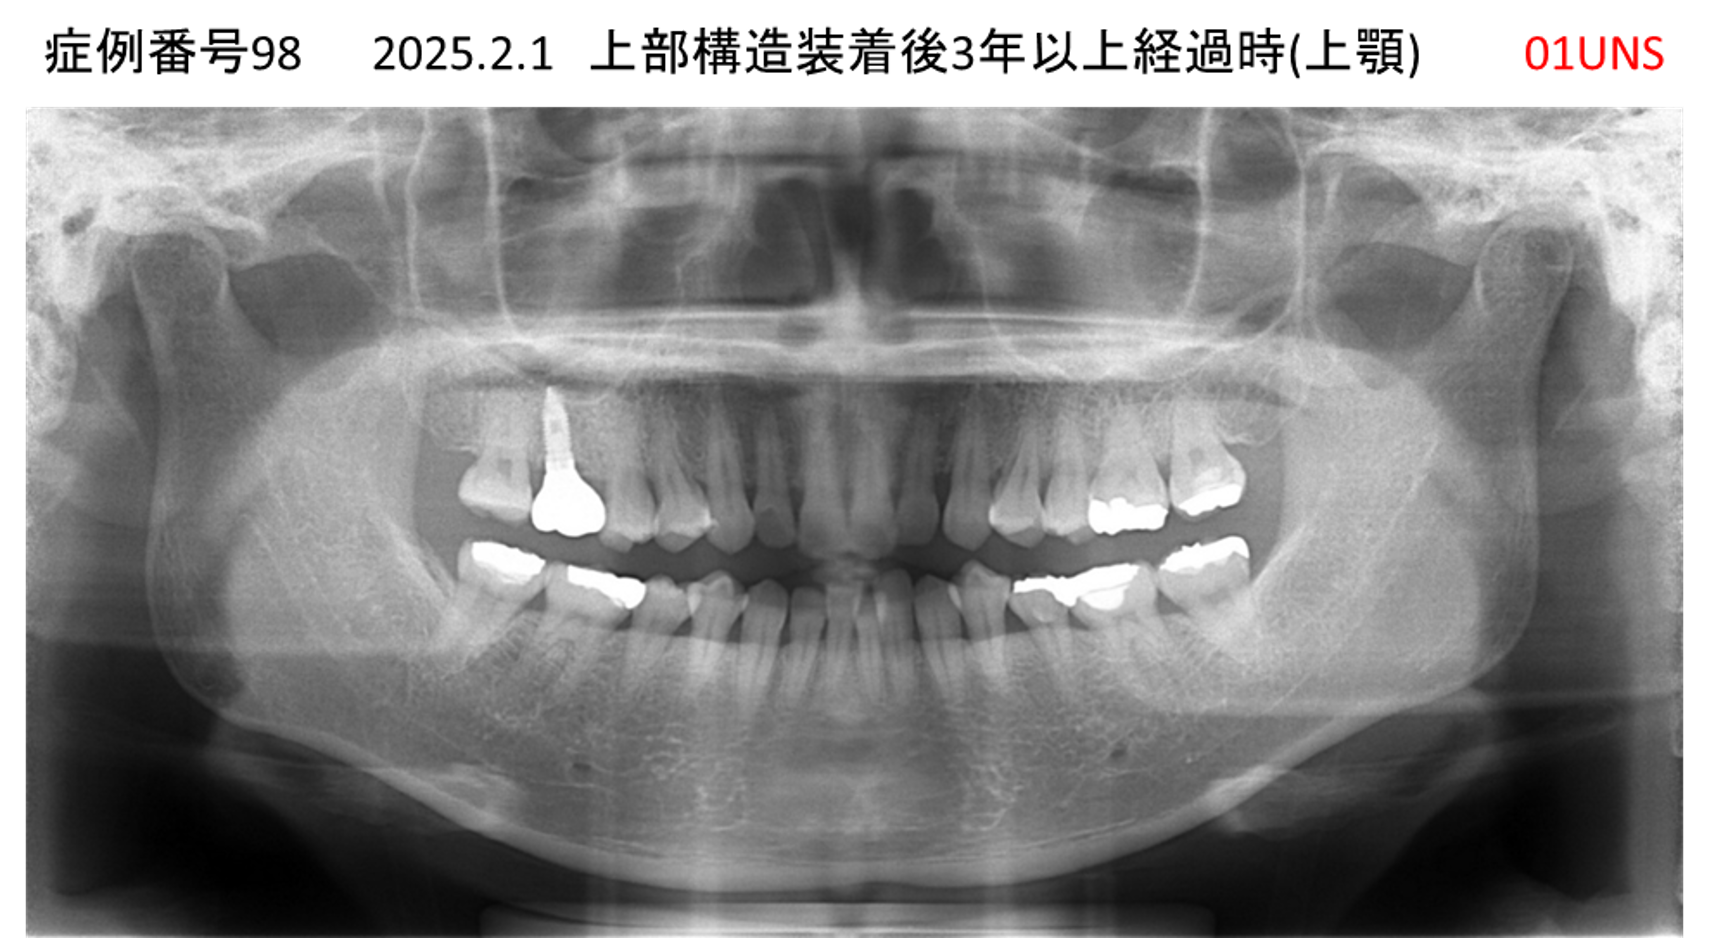

上の前歯が揺れてきてかめない患者様のインプラント症例

| 治療名称 |

インプラント |

| 治療費用 |

440万円+税 |

| 治療期間 |

6か月 |

| 患者さんの症状(主訴) |

上の前歯が揺れてきた。かめない |

| 治療内容 |

サイナスリフト、GBR、インプラント、即時荷重 |

| 治療結果 |

上の前歯の揺れが収まった。奥歯でしっかり噛める。 |

| 治療の注意点(リスク/副作用) |

インプラントが壊れたら再治療が必要 |